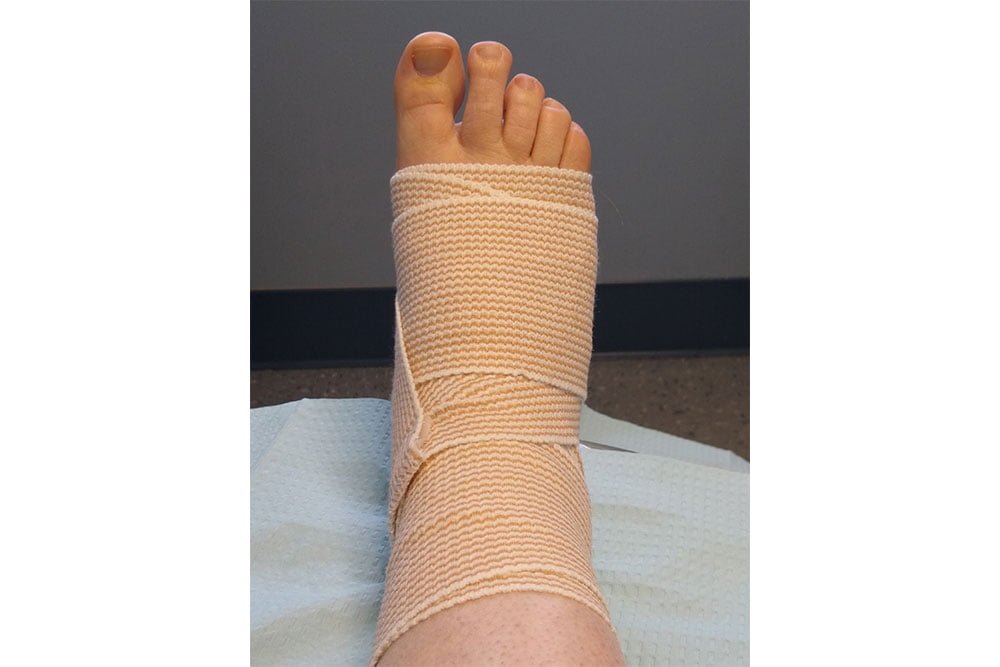

- Fracture and trauma management, including durable medical equipment (DME)